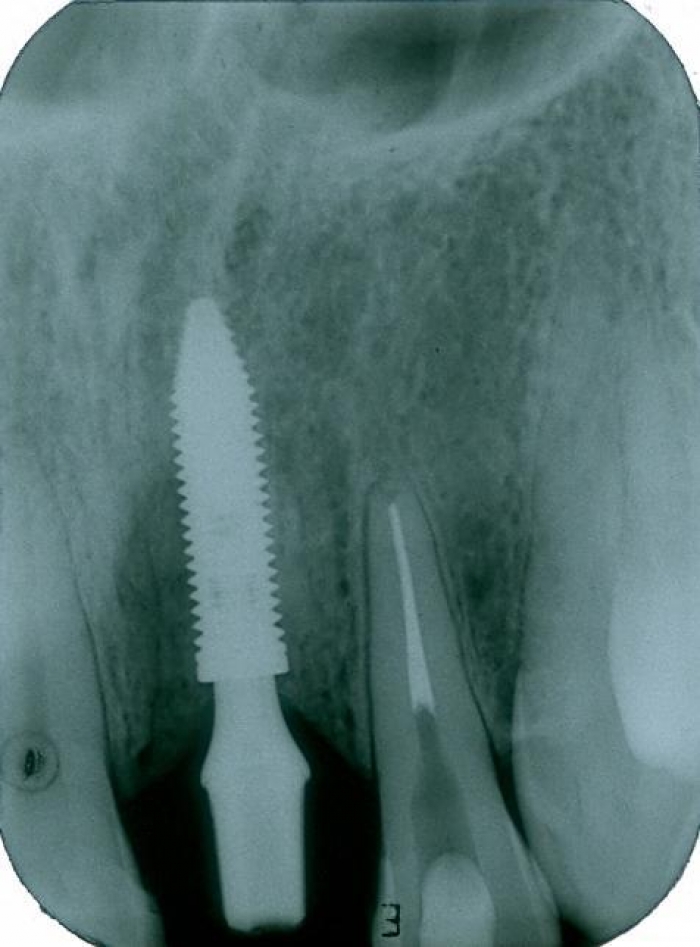

Raio X do implante instalado